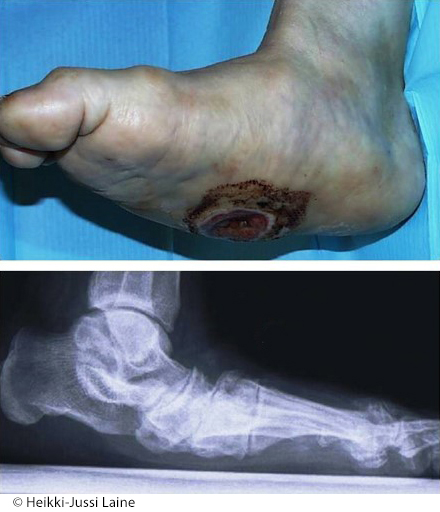

Amputaatiodeformiteetteja. Amputaation jälkeisiä rakennemuutoksia ja niiden aiheuttamia painehaavoja diabe testa sairastavan jalassa.

© Heikki-Jussi Laine

Amputaatiodeformiteetteja